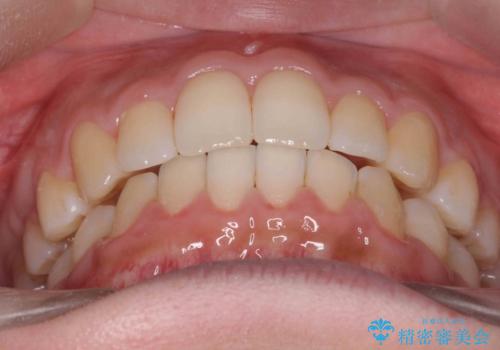

- 出っ歯を主訴に来院。

上の歯を全体に大きく後ろに下げる治療計画を立てました。

後ろに下げるために、親知らずは抜歯しています。

後ろに下げるために、ワイヤー矯正の前にカリエールという装置を使用しました。